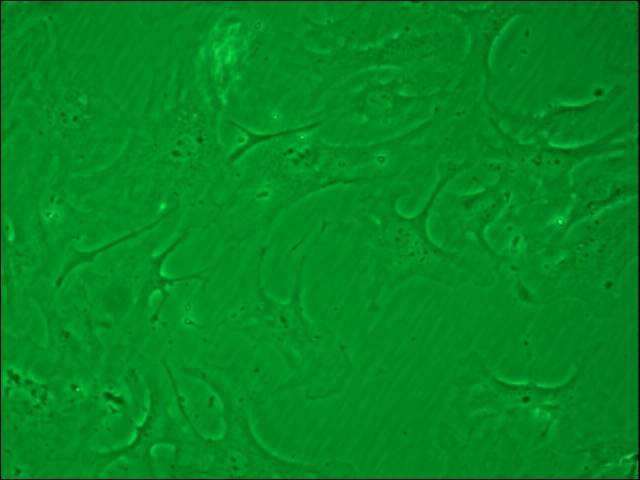

Çó´óʦÃǰïæ¼ø¶¨Ò»ÏÂÊDz»ÊÇÐÉÏËάϸ°û ÒÑÓÐ2È˲ÎÓë